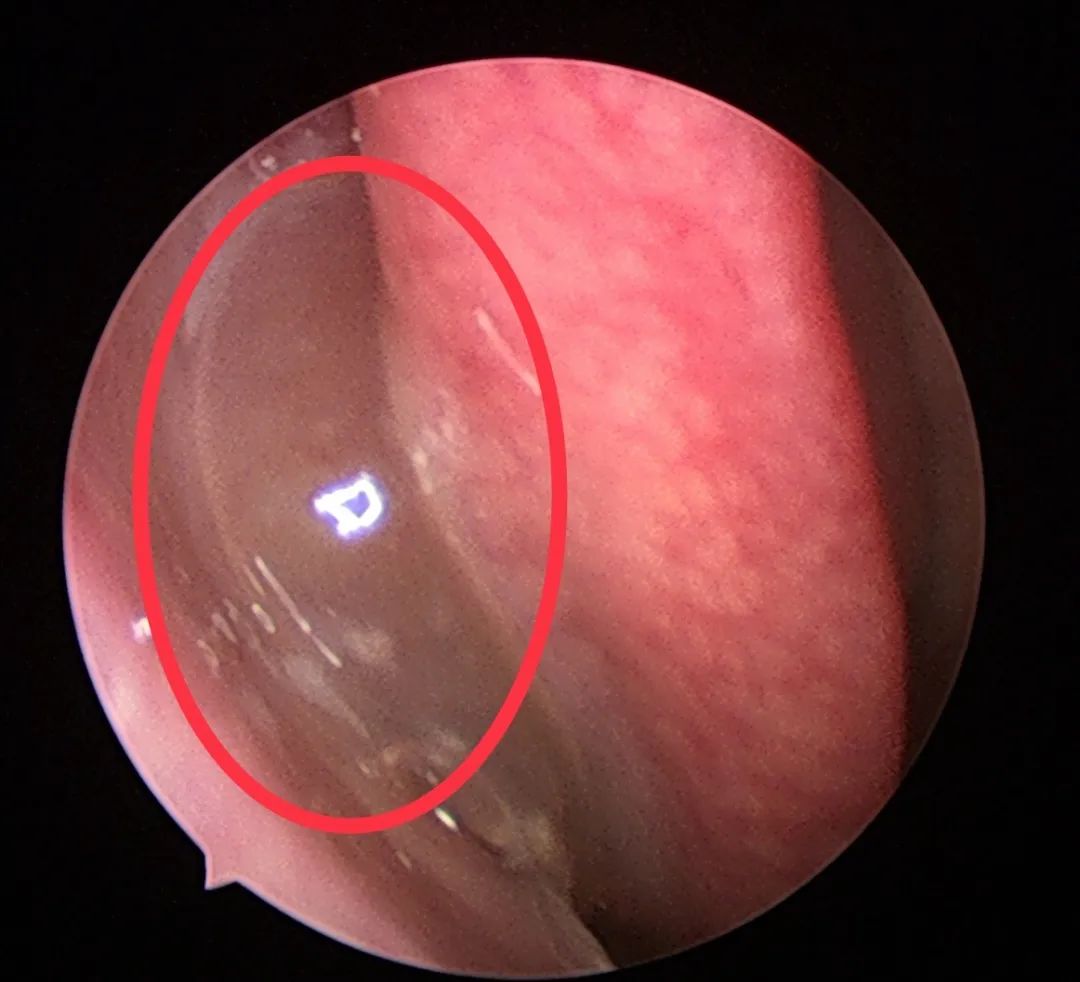

既然这多人都那么怕鼻息肉,那么真正的鼻息肉是啥样子的呢?

下面,我们来看看真正鼻息肉的面目:

其实,鼻息肉之所以让人们觉得那么恐怖,是因为它难以治根,经常复发。近年来,随着鼻内镜微创手术的开展,手术的效果还是不错的。